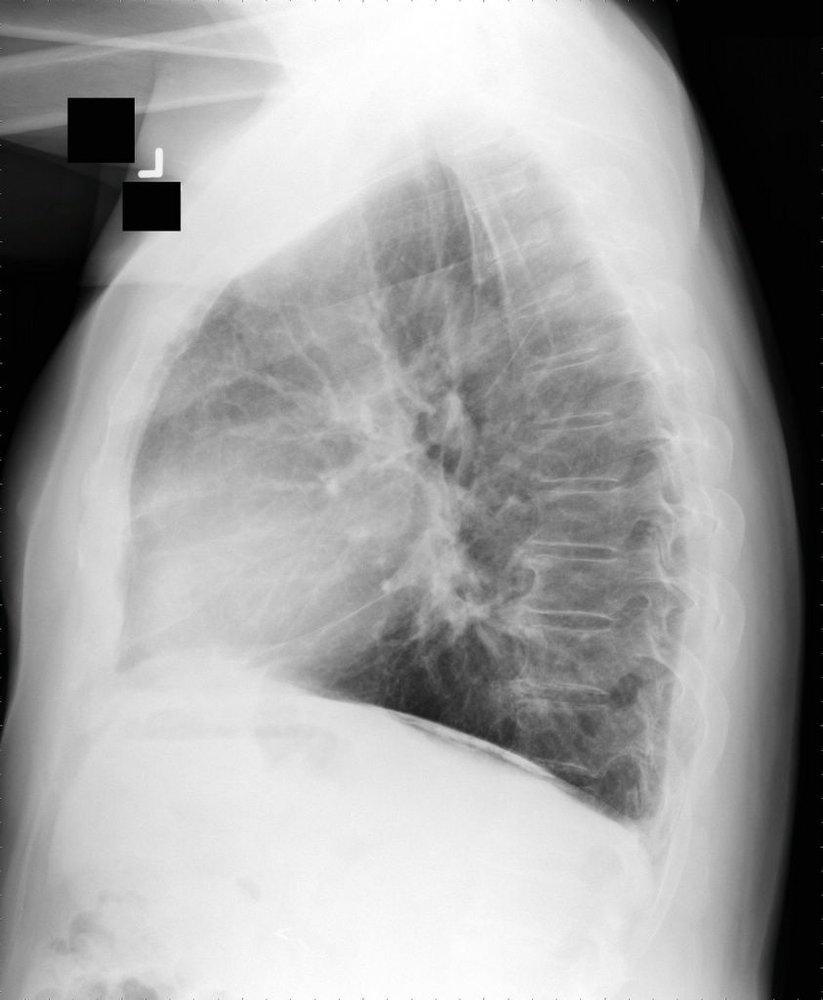

Chest x-ray is often performed as part of a routine workup for respiratory symptoms, however, HRCT has higher sensitivity and specificity (especially in early disease stages).

• Chest x-ray

• Signs of interstitialfibrosis (e.g., diffuse bilateral opacities, predominantly in the lower lobes)

• Pleural abnormalities (e.g., pleural plaques and pleural thickening) may be seen.

• HRCT

• Signs of interstitial fibrosis, e.g.:

• Subpleural linear opacities

• Septal and interlobular thickening

• Honeycombing

• Rounded atelectasis

• Pleural abnormalities

• Calcified (ivory white) or noncalcified pleural plaques

• Pleural reticulonodular opacities

• Pleural thickening

Although asbestos is commonly found in roofing materials, it predominantly affects the lower lobes of the lungs.